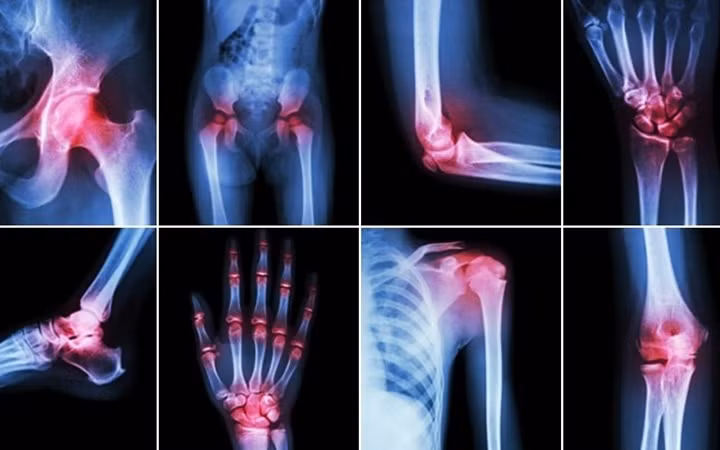

Viêm khớp : Mùa Đông cũng là khắc tinh của những người bị đau khớp. Những người bị viêm khớp cho biết, các khớp xương của họ cứng hơn và bị đau hơn vào mùa Đông. Tuy nhiên, không có cơ sở nào chứng minh rằng thời tiết lạnh hơn sẽ gây ra bệnh đau khớp. Một số chuyên gia cho rằng, con người bị trầm cảm hơn trong thời tiết mùa Đông, khiến họ cảm nhận nỗi đau sâu sắc hơn. Các chuyên gia đưa ra lời khuyên rằng, việc tập thể dục hàng ngày có thể giúp cải thiện thể chất và cả tinh thần của người bệnh. Bơi lội là môn thể thao lý tưởng cho những người có vấn đề về khớp. Ảnh: KT